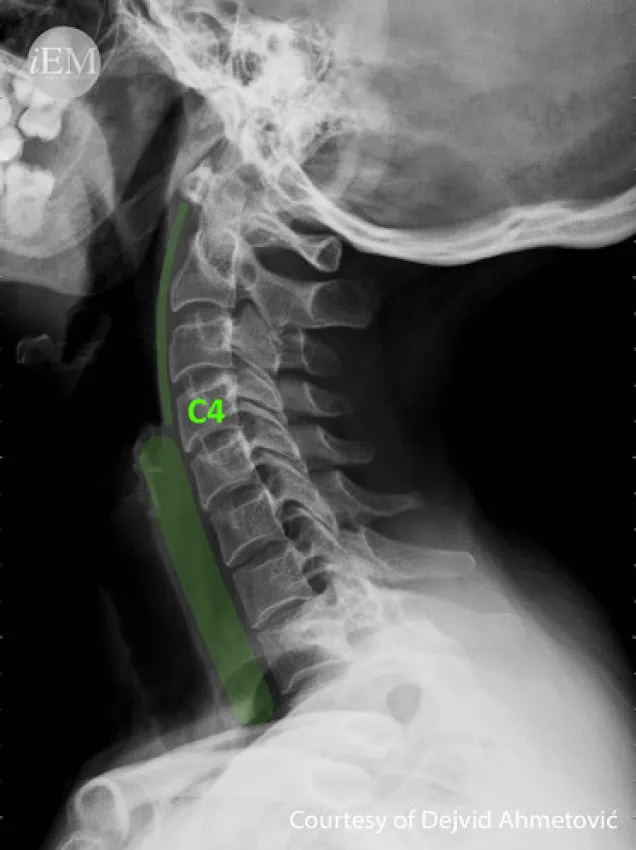

X-ray of the cervical spine, AP, and LAT view test is used to visualize the first seven vertebral bones (C1 - C7) of the spinal column (backbone) located in the neck region. These bones are referred to as the cervical vertebrae.

This examination is recommended to identify the source of the patient's neck pain, check for damage to the vertebrae in the spine, diagnose any possible spinal tumours or infections, and identify any potential disc issues.